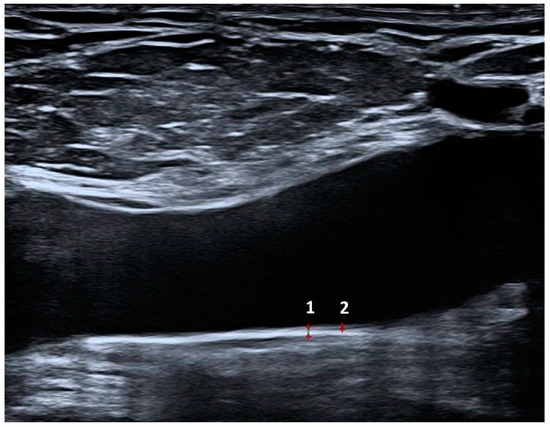

2.3. Venous Doppler Ultrasonography

All Doppler US examinations were performed on the same day as the clinical assessment by a single expert radiologist with eight years of US experience who was blinded to the cases (Y.S.). Bilateral lower extremity veins (the CFV, superficial femoral vein, popliteal vein, and great saphenous vein) were examined in the craniocaudal direction using a high-resolution Doppler US system (Aplio i800; Canon Medical Systems, Tokyo, Japan) equipped with a high-resolution linear transducer (14–18 MHz). The hip was externally rotated, and the knee was slightly rotated to reveal deep veins and reduce muscle tension. Deep and superficial lower extremity veins were examined for the presence or absence of chronic thrombotic changes, venous insufficiency, recanalization, reflux, and collateral development. In supine and prone positions, venous insufficiency was assessed following the Valsalva maneuver in the saphenofemoral junction and popliteal veins. VWT and IMT of the CFV measurements were performed 2 cm distal to the saphenofemoral junction in the supine position from the posterior wall of the vessel to avoid reverberation artifacts. Anterior wall examination was not performed, as it may cause reverberation artifacts that would result in an imperfect delineation. IMT measurements were performed from the blood–intima interfaces to the outer end of the hypoechoic line (media–adventitia junction). The adventitial layer was excluded from the IMT measurement. Two measurements were taken from each vessel, and the average value was noted. WWT and IMT measurements of CFV are shown in Figure 3.

Figure 3. The measurement of the common femoral vein whole-wall (1) and intima–media thickness (2) in a patient with Behçet’s Disease.